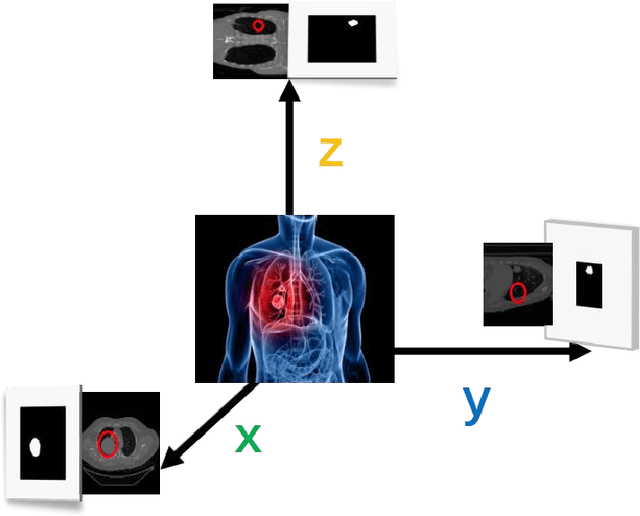

A Radiogenomics Pipeline for Lung Nodules Segmentation and Prediction of EGFR Mutation Status from CT Scans

Nov 12, 2022

Lung cancer is a leading cause of death worldwide. Early-stage detection of lung cancer is essential for a more favorable prognosis. Radiogenomics is an emerging discipline that combines medical imaging and genomics features for modeling patient outcomes non-invasively. This study presents a radiogenomics pipeline that has: 1) a novel mixed architecture (RA-Seg) to segment lung cancer through attention and recurrent blocks; and 2) deep feature classifiers to distinguish Epidermal Growth Factor Receptor (EGFR) mutation status. We evaluate the proposed algorithm on multiple public datasets to assess its generalizability and robustness. We demonstrate how the proposed segmentation and classification methods outperform existing baseline and SOTA approaches (73.54 Dice and 93 F1 scores).